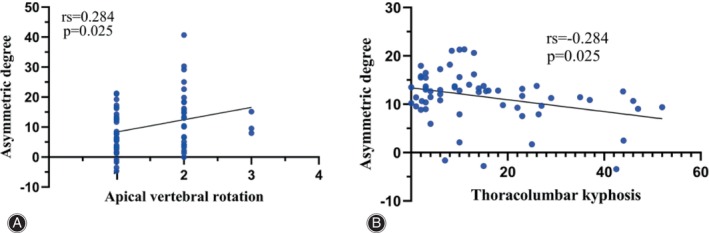

The asymmetric degree (AD) in the change of the multifidus was significantly higher at the apex of both the main and fractional curves compared to the erector spinae (Z = ‐4.839, p < 0.05; Z = ‐2.695, p < 0.05). The change in AD of the erector spinae was weakly positively correlated with the AVR (0 < rs <1, p < 0.05), while that of MS was weakly negatively correlated with TLK in Type A (−1 < rs <0, p < 0.05) (Fig. 4). The change in AD of the erector spinae was strongly positively correlated with CBD at the apex of the main curve in Type B (0 < r < 1, p < 0.05) (Fig. 5). At the apex of the fractional curve, the change in AD of the erector spinae was strongly positively correlated with CBD (0 < rs <1, p < 0.05), and the change in AD of the multifidus was strongly positively correlated with AVR (0 < rs <1, p < 0.05), while it was strongly negatively correlated with PI and SS (−1 < r < 0, p < 0.05) in Type C (Fig. 6).

A prior study has established that the primary function of the multifidus muscle is to maintain the posterior sagittal rotational balance of the lumbar vertebrae.ref. os14185-bib-0030 In our current investigation, we observed a strong positive correlation between the degree of asymmetry in multifidus muscle changes and the AVR. Notably, there exists a negative correlation between qualitative muscle changes caused by fat infiltration and muscle strength.ref. os14185-bib-0036 The unopposed action of the deep spinal transverse and rotator muscles is a significant factor in initiating deformities in many idiopathic curves.ref. os14185-bib-0037 We hypothesize that this mechanism also operates in DLS. Conversely, this asymmetry showed a strong negative correlation with the PI and SS in Type C. Paravertebral muscles attach to the sacrum as they pass between the lumbar vertebrae and ilium. It seems reasonable that the larger the size of the multifidus, the greater the strength, and thus the greater the PI and SS angle. As is well known, there exists a negative correlation between qualitative muscle changes caused by fat infiltration and muscle strength. Because of the negative correlation between fat infiltration and muscle strength, the correlation between the multifidus fat infiltration and PI or LL is logical. Minetama et al. and Menezes‐Reis et al.ref. os14185-bib-0011, ref. os14185-bib-0012 identified that multifidus volume was positively correlated with PI and SS (I = 0.22; 0.08), and its fat infiltration was negatively correlated with PI (I = −0.11) in asymptomatic adults, in line with our findings. While they also found multifidus fat infiltration was positively correlated with SS (r = 0.15). The cause of the discrepancy with our results might be interpreted by the different diseases and study design. We believe that, in addition to coronal imbalance, these pelvic parameters can exacerbate paravertebral muscle degeneration.

It is not surprising that the degree of asymmetry in multifidus muscle changes positively correlated moderately with AVT in Type C, while the degree of asymmetry in erector spinae changes weakly correlated positively with AVR in Type A, as lateral vertebral translation often deviates from the concave side, and the unopposed action of deep spinal transverse and rotator muscles plays a significant role in these processes. Current guidelines stress the importance of addressing sagittal imbalance, but it is equally crucial not to disregard the coronal component. In our study, we observed that 26.2% of DLS patients displayed pre‐operative coronal imbalance among the 84 patients in our sample, which aligns with previous findings.ref. os14185-bib-0023, ref. os14185-bib-0038 Based on the CBD, we categorized patients as having either coronal balance (CBD < 3 cm) or coronal imbalance (CBD > 3 cm).ref. os14185-bib-0023, ref. os14185-bib-0039 In this investigation, Type B and Type C exhibited significantly greater CBD compared to Type A. Moreover, the asymmetrical degeneration of paraspinal muscles is linked to spine instability and may contribute to the progression of scoliosis.ref. os14185-bib-0006 Conversely, spinal deformity may also play a role in the development of fat infiltration in paraspinal muscles.